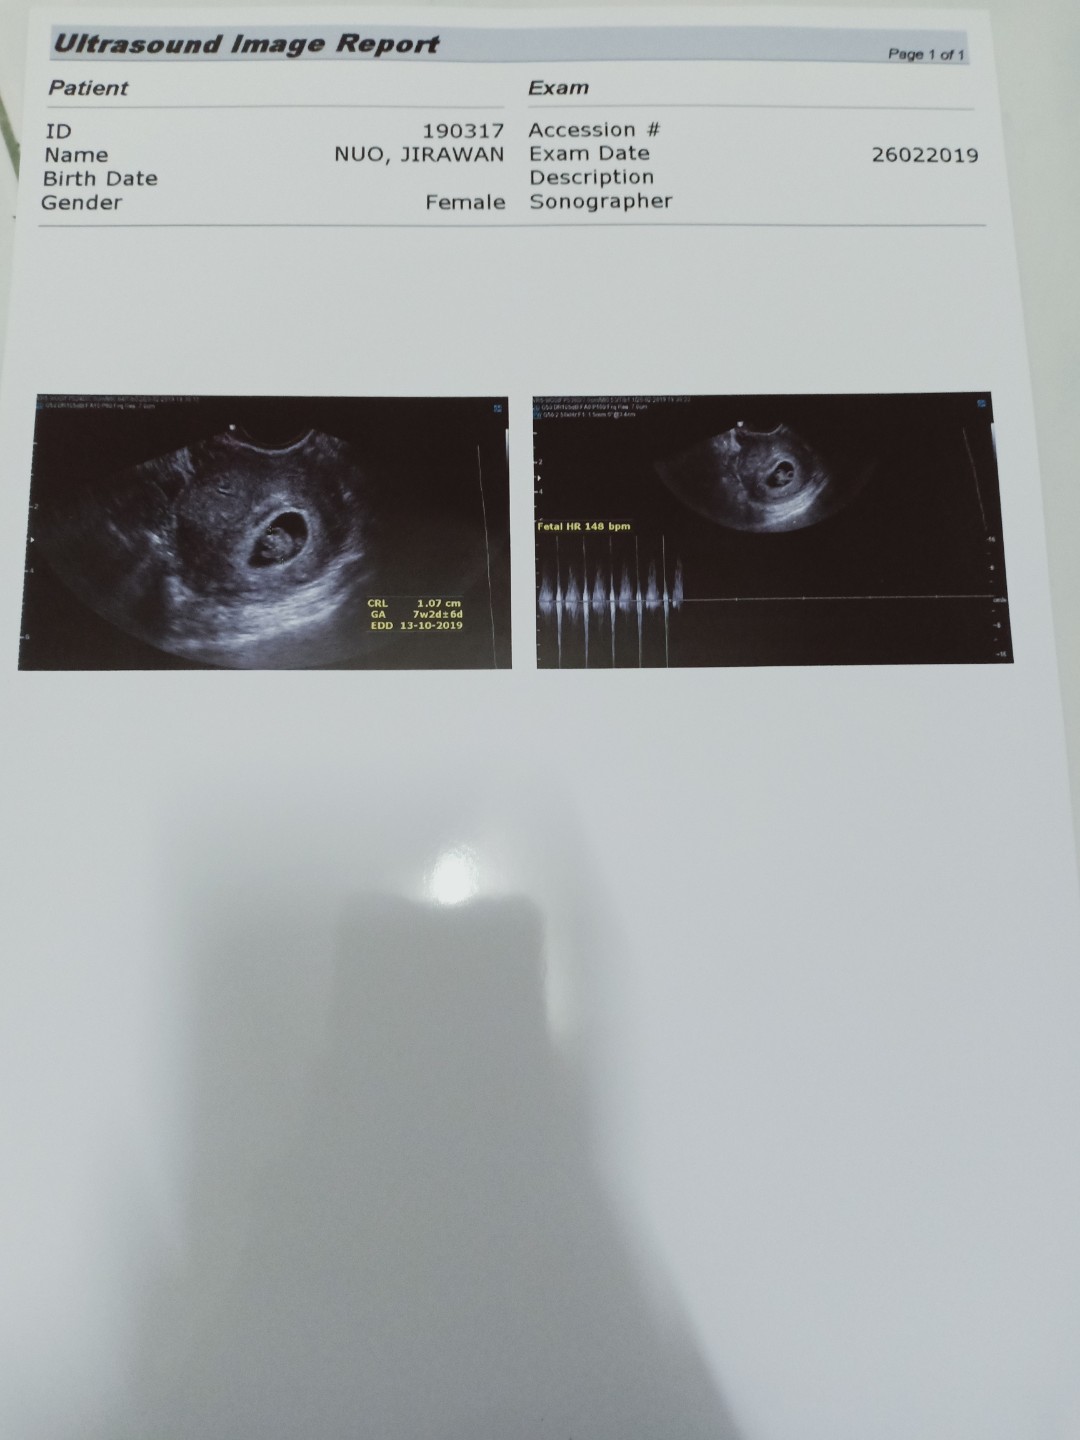

7week

7week